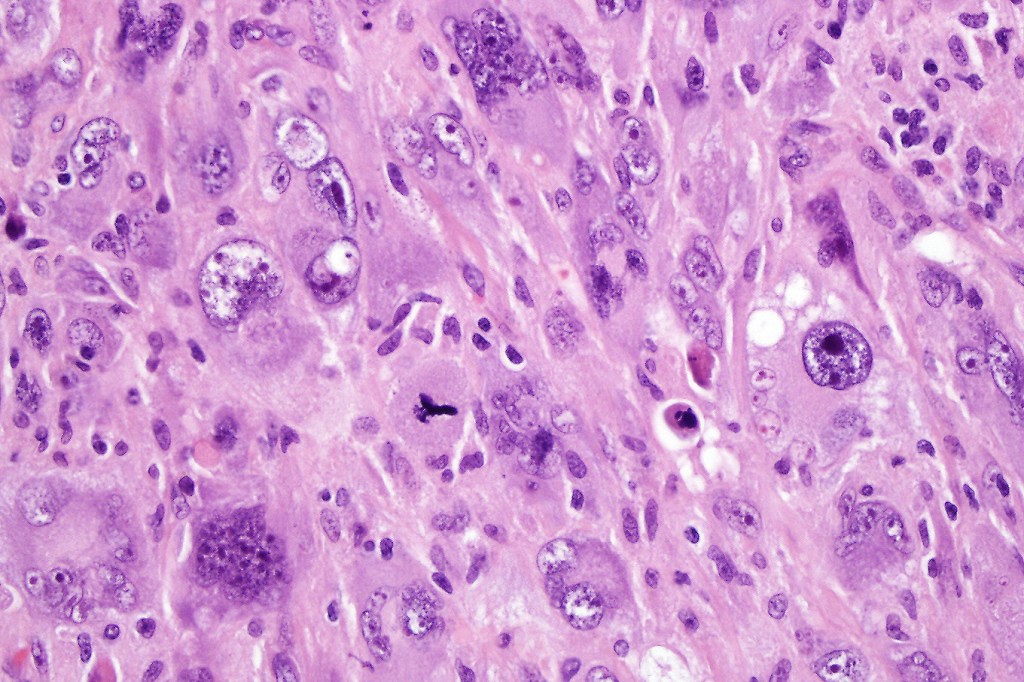

Carcinosarcoma

Cutaneous carcinosarcoma (metaplastic carcinoma, carcinoma with heterologous differentiation)

Histological features

•Osteoid

•Chondroid

•Smooth muscle

•MFH-like features with osteoclasts

•Neural differentiation